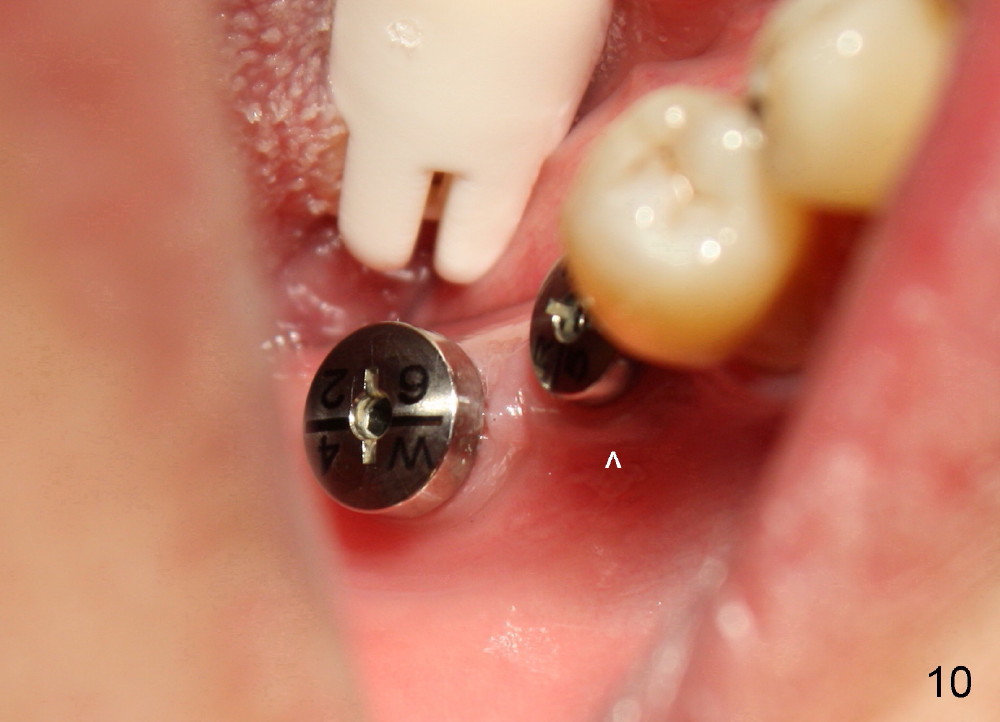

Finally 5.3x10 mm SM implant is placed at #31 (Fig.7). Healing abutments (Ɵ5.2x3(1) and 6.2x4(2) mm) are placed at #30 and 31, respectively (Fig.7-9).

One week postop, the gingiva buccal to #30 healing abutment was reddish (at the area indicated by arrowheads in Fig.10,11). The patient complained facial swelling. Clindamycin was taken one extra week to help resolve postop infection. By 24 days postop, there is no infection around these two healing abutments (Fig.10-12). The patient is pleased and makes an appointment for #18 implant placement (Fig.1), which is more challenging.